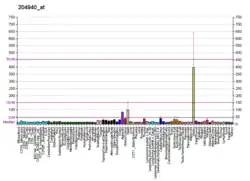

Phospholamban, also known as PLN or PLB, is a micropeptide protein that in humans is encoded by the PLN gene.[5] Phospholamban is a 52-amino acid integral membrane protein that regulates the calcium (Ca2+) pump in cardiac muscle cells.[6]

This protein is found as a pentamer and is a major substrate for the cAMP-dependent protein kinase (PKA) in cardiac muscle. In the unphosphorylated state, phospholamban is an inhibitor of cardiac muscle sarcoplasmic reticulum Ca2+-ATPase (SERCA2)[7] which transports calcium from cytosol into the sarcoplasmic reticulum. When phosphorylated (by PKA) - disinhibition of Ca2+-ATPase of SR leads to faster Ca2+ uptake into the sarcoplasmic reticulum, thereby contributing to the lusitropic response elicited in heart by beta-agonists.[8] The protein is a key regulator of cardiac diastolic function. Mutations in this gene are a cause of inherited human dilated cardiomyopathy with refractory congestive heart failure.[9]

When phospholamban is phosphorylated by PKA, its ability to inhibit SERCA2 is lost.[10] Thus, activators of PKA, such as the beta-adrenergic agonist epinephrine (released by sympathetic stimulation), may enhance the rate of cardiac myocyte relaxation. In addition, since SERCA2 is more active, the next action potential will cause an increased release of calcium, resulting in increased contraction (positive inotropic effect). When phospholamban is not phosphorylated, such as when PKA is inactive, it can interact with and inhibit SERCA. Thus, the overall effect of unphosphorylated phospholamban is to decrease contractility and the rate of muscle relaxation, thereby decreasing stroke volume and heart rate, respectively.[11]

PLN has been shown to interact with SLN[16][17] and SERCA1.[17][18][19]